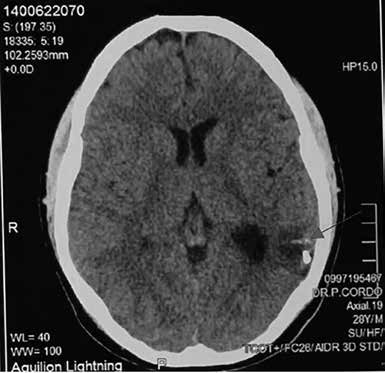

Figura 3. Tomografía multicorte de cráneo posembolización. Se evidencia área

hipodensa en región temporo-occipital izquierda con presencia de calcificaciones

en su interior, acompañada de una ligera retracción del asta posterior del

ventrículo lateral

Se le realiza control

al mes de la embolización y se evidencia reabsorción de 1/3 del

coagulo hemático sin alteraciones en el examen físico y neurológico. A los

tres meses, en la tomografía el paciente presenta reabsorción total de hemorragia intraparenquimatosa causada por MAV; sin embargo, existe presencia de una pequeña área de

encefalomalacia a nivel temporo-occipital izquierdo, que está produciendo la retracción de la asta posterior del ventrículo lateral y presencia de calcificaciones del mismo lado.

No se visualizan hematomas extraaxiales y existe

una adecuada diferenciación entre la sustancia gris y sustancia blanca. Las estructuras del parénquima cerebral, de la fosa posterior y del tronco

del cerebro están conservadas y sin alteraciones (ver Figura 3).